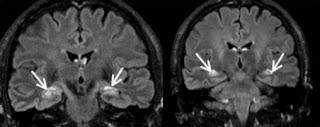

Encéphalite limbique: IRM pondérée en séquence Flair. Coupes coronales retrouvant des hypersignaux bitemporaux (flèches blanches). In La revue de médecine interne Volume 32, Issue 12, December 2011, Pages 742 - 750